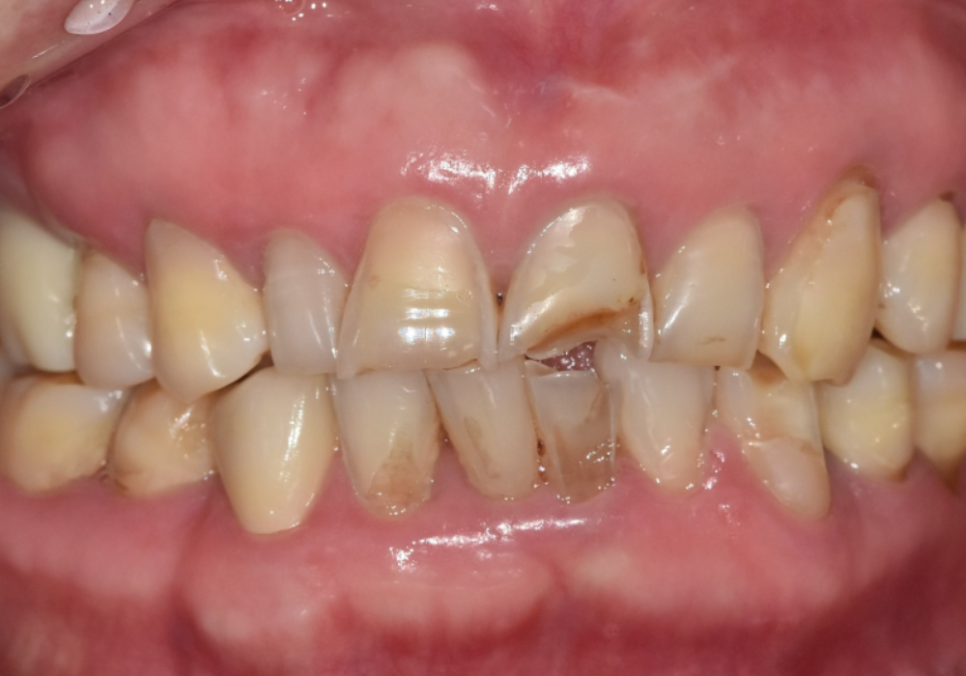

입안을 직접 살펴보니

굳이 말씀을 안 하셔도...

평소 식습관을 알 수 있을 정도였는데요~

치아의 씹는 면이

맷돌처럼 평평하게 마모되어 있었고

군데군데 작게 깨진 흔적들도 많았거든요.

251229

특히 치아와 잇몸이 만나는 목 부위가

도끼로 찍은 듯 파여있는

치경부 마모 증상도 관찰되었습니다.

강한 힘으로 음식을 씹을 때

치아가 미세하게 휘어지면서

가장 약한 목 부분이 떨어져 나가는 현상이죠.

이는 딱딱한 음식을 즐기는 분들에게

흔히 나타나는 징후들입니다.